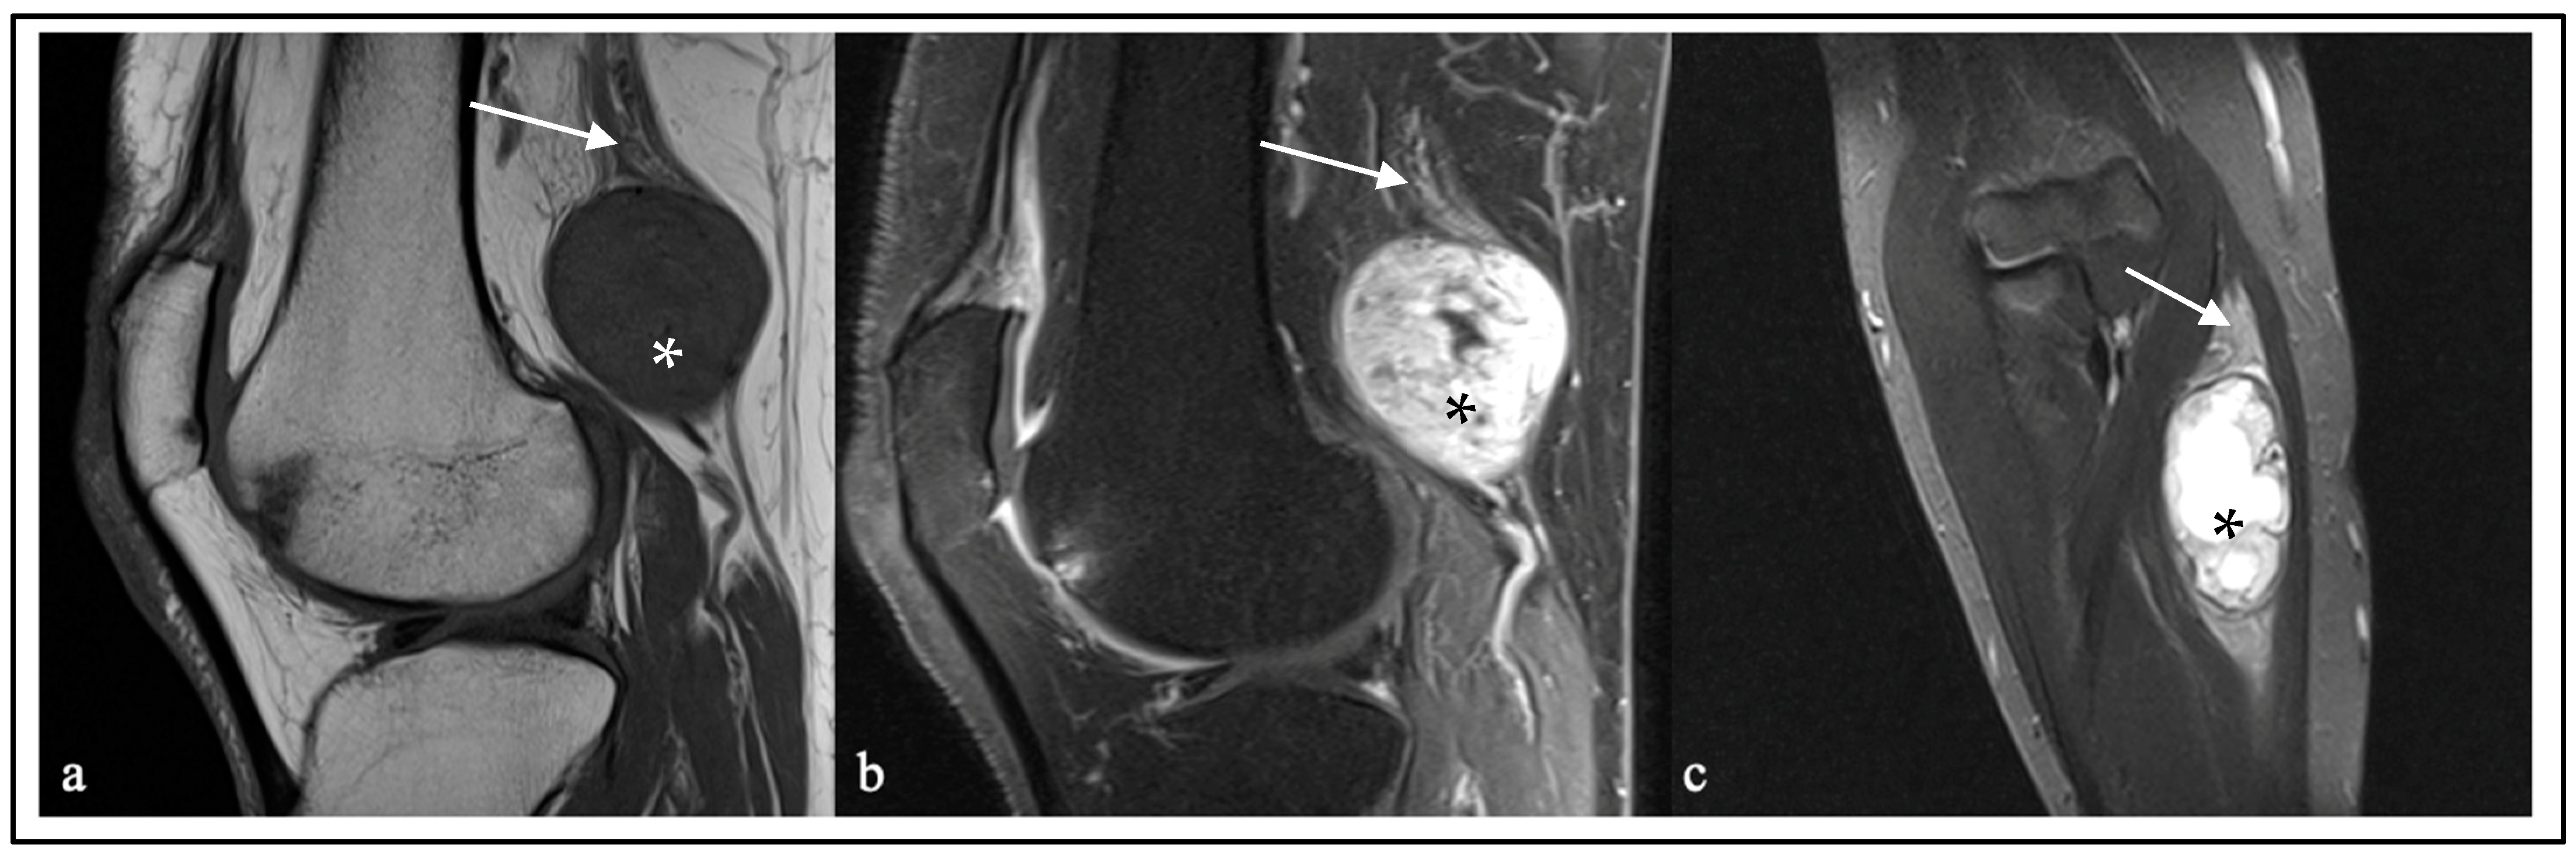

| Diagnosis | MRI Features | Lesion Component in T2 | ||||

|---|---|---|---|---|---|---|

| Size * (mm), Range, Mean | Contrast Enhancement (n, %) | Invasion (n, %) | Cystic (n, %) | Ih (n, %) | H (n, %) | |

| Intrinsic PNTs | ||||||

| HPNST (n = 13) | 19–76 (41) | 13 (100%) | 0 | 5 (38%) | 12 (92.3%) | 1 (8%) |

| HPNST (S/NF) (n = 11) | 19–76 (40) | 11 (100%) | 0 | 4 (36%) | 10 (91%) | 1 (9%) |

| HPNST (S/P) (n = 2) | 23–71 (47) | 2 (100%) | 0 | 1 (50%) | 2 (100%) | 0 |

| MPNST (n = 13) | 27–96 (57) | 13 (100%) | 3 (23%) | 7 (53%) | 12 (92%) | 1 (8%) |

| Perineurioma (n = 17) | 15–190 (72) | 17 (100%) | 0 | 14 (82%) Enlarged fascicles and/or change in calibers | ||

| ANNUBP (n = 1) | 52 | 1 (100%) | 0 | 0 | 1 (100%) | 0 |

| Extrinsic PNTs | ||||||

| Metastatic tumor (n = 1) | 80 | 1 (100%) | 1 (100%) | 1 (100%) | 1 (100%) | 0 |

| Lymphoma (n = 3) | 21–120 (81) | 3 (100%) | 2 (67%) | 0 | 3 (100%) | 0 |

| Amyloidoma (n = 1) | 29 | 1 (100%) | 0 | 0 | 0 | 1 (100%) |

| Hemangioma (n = 1) | 140 | 1 (100%) | 1 (100%) | 1 (190%) | 1 (100%) | |

| Angiomatosis (n = 1) | 12 | 0 | 0 | 0 | 0 | 1 (100%) |

| Capillary hemangioma (n = 1) | 7 | 0 | 0 | 0 | 0 | 1 (100%) |

| EHE (n = 1) | 28 | 1 (100%) | 1 (100%) | 1 (100%) | 1 (100%) | |

| SFT (n = 2) | 29–57 (43) | 2 (100%) | 0 | 2 (100%) | ||

| Lymphangioma (n = 2) | 48–82 (65) | 2 (100%), honeycomb-like | 0 | 2 (100%), honeycomb-like | 0 | |

| Desmoid (n = 1) | 49 | 1 (100%) | 1 (100%) | 0 | 0 | 1 (100%) |

| Myopericytoma (n = 1) | 10 | 1 (100%) | 0 | 0 | 0 | 1 (100%) |